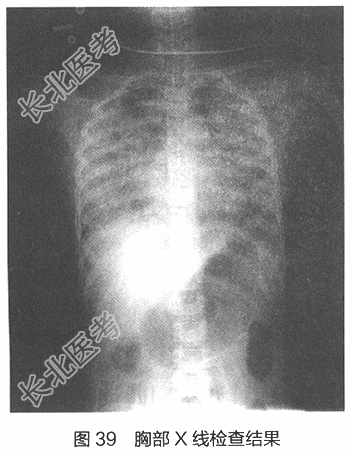

- 多项选择题4.[提示]血常规:外周血WBC 0.8×109/L, N 0.60,Hb 72g/L, PLT 70×109/L,CRP> 160mg/L;血气分析: pH 7.36,PaO2 56mmHg, PaCO2 28mmHg,BE-5mmol/L(FiO2 60%)。胸部X线片如图39所示。结合病史, 考虑诊断为

A、DIC合并肺出血

B、重症肺炎合并心力衰竭

C、严重脓毒症合并ARDS

D、急性左侧心力衰竭

E、脑炎合并神经源性肺水肿

F、肺透明膜病